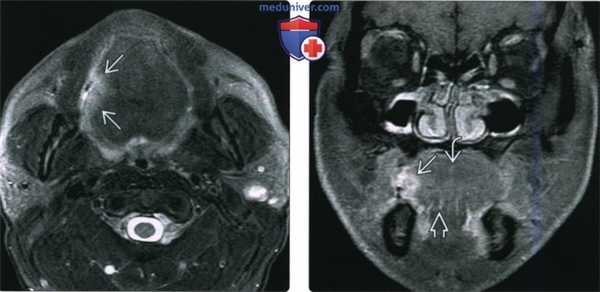

(Слева) При МРТ Т1ВИ С + FS в аксиальной проекции у этого же пациента не четко визуализируется объемное образование передних отделов дна полости рта, прорастающее в правую подъязычную железу. Обратите внимание на отсутствие кортикальной пластинки с гипоинтенсивным сигналом в прилежащих отделах нижней челюсти, что подтверждается и при КТ в костном окне. Патологически измененные лимфоузлы не определяются.

(Слева) При MPT Т2ВИ FS в аксиальной проекции визуализируется небольшая опухоль в боковых отделах языка справа, выглядящая как двояковыпуклый участок с сигналом повышенной интенсивности и с типичными нечеткими краями, недостигающий средней линии.

(Справа) Корональная томограмма (Т1ВИ С+ FS) этого же пациента, язва в боковых отделах языка накапливает контраст. Опухоль не распространяется книзу в подбородочно-язычную мышцу или в другие наружные мышцы языка, и не достигает срединно расположенной язычной перегородки. Была выполнена гемиглоссэктомия и селективная шейная лимфодиссекция, подтвердился ПКР (Т1 N0, первая стадия).